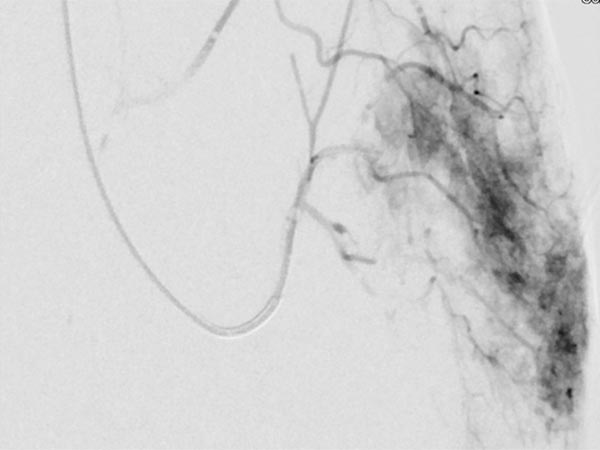

Auch in der Übersichtsangiographie über die linke Arteria iliaca externa zeigt sich keinerlei Perfusion des Tumors mehr, die Tumorvaskularisation ist somit erfolgreich superselektiv vollständig verschlossen. Alle nicht pathologischen Arterien sind erhalten.